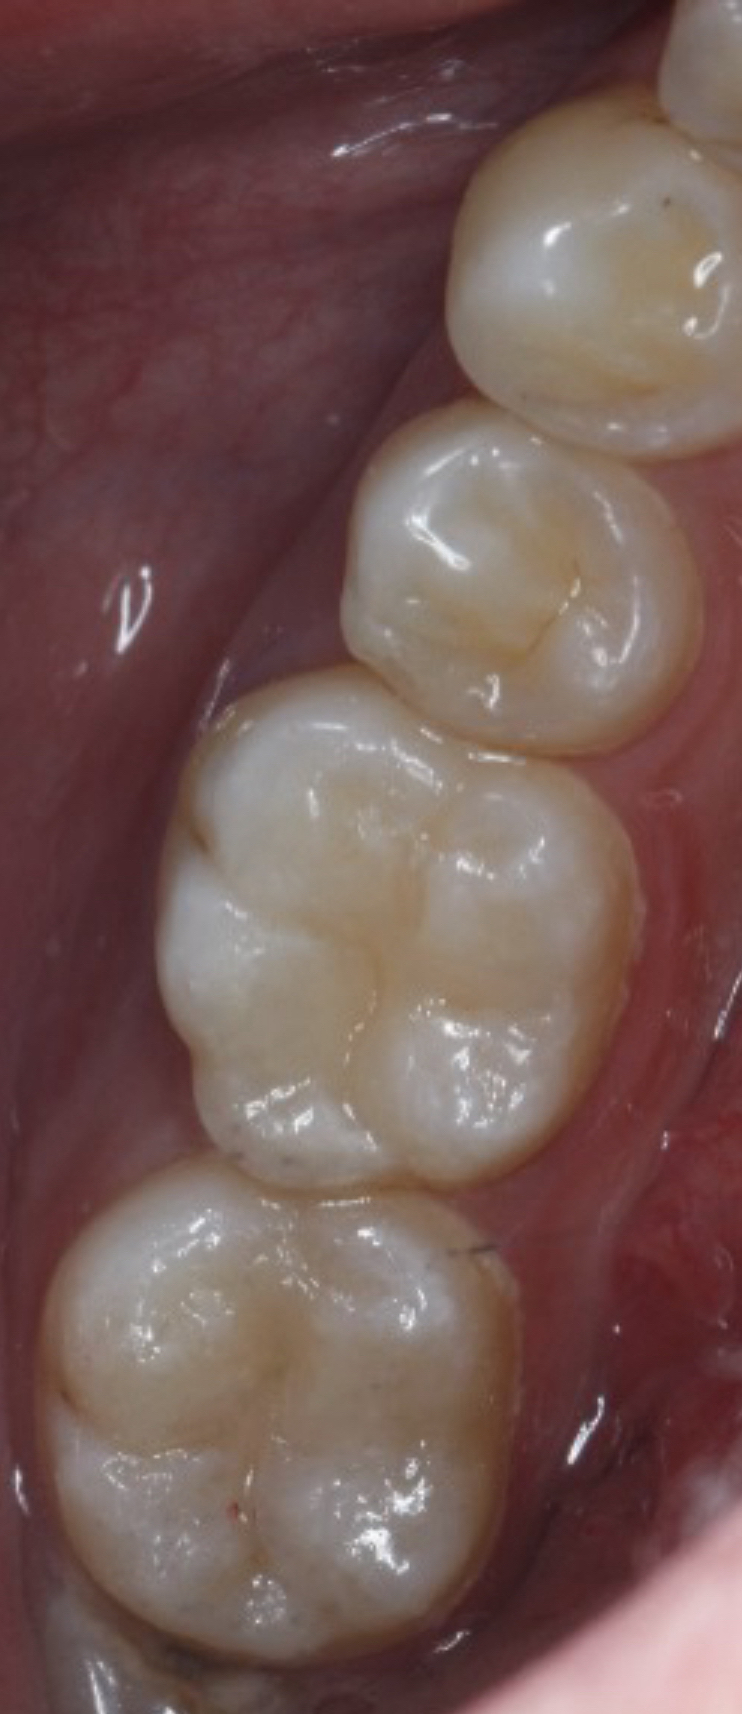

清洁窝洞后,填入补牙材料(如树脂、玻璃离子等),塑形并固化。

4. 抛光调整

调整咬合高度,抛光表面,恢复牙齿自然外观。

1. 复合树脂

- 优点:颜色接近真牙,美观耐用,适合前牙。